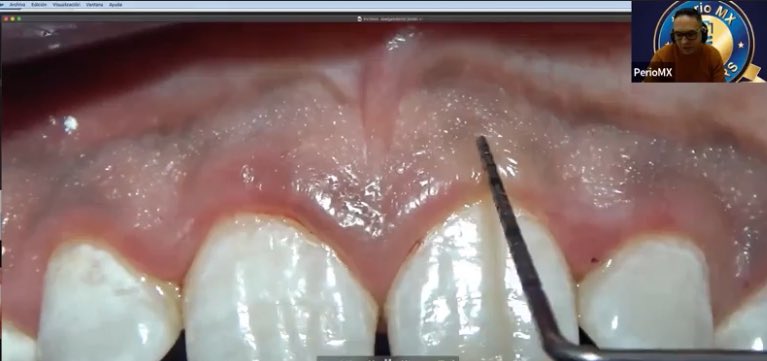

Para hacer una incisión debemos reconocer biológicamente varios parámetros, uno de ellos es si el frenillo conlleva algún defecto. #cursodeincisión #PerioMX #periomembers #frenillo

PerioMX's tweet image. Para hacer una incisión debemos reconocer biológicamente varios parámetros, uno de ellos es si el frenillo conlleva algún defecto.